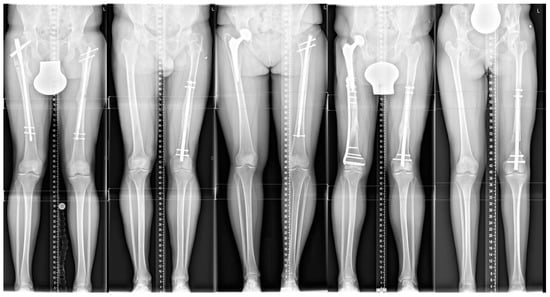

After applying the exclusion criteria, five patients (two men and three women) with a mean age of 28 years and a mean LLD of 36 mm were left for final analysis. Demographic data and baseline characteristics are presented in Table 1, a patient’s list in Table 2. Figure 1 shows the patient’s X-rays.

Figure 1. Long-standing radiographs are presenting all five patients (1 to 5).